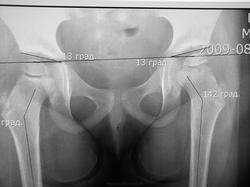

Первоначально обратились с жалобами на боли в левой ноге возникающей утром, в течении 3-х месяцев. В клинической картине походка не нарушена, отмечается укорочение левой ноги 0,5см., приводящяя контрактура бедра, гипотрофиии нет. Вальгусная деформация коленных суставов и стоп. Смущает возраст и пол ребенка. Выставил диагноз Болезнь Пертеса.

Согласна, слева Пертес. А каков возраст девочки?

Возраст девочки 3года 6 месяцев. УЗИ тазобедренных суставов( 02.03.13)- признаки болезни Пертеса.

Похоже, болезнь Пертеса.